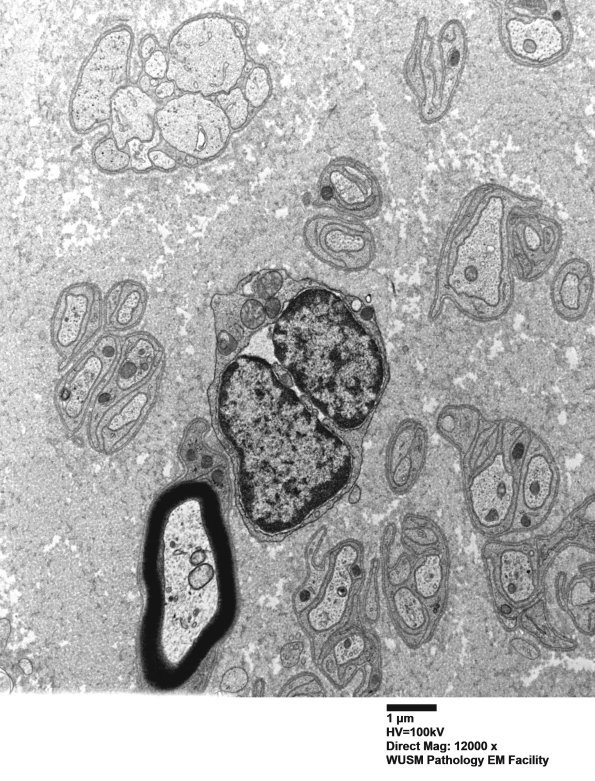

Axon loss accompanied by axonal depopulation of Schwann cells, residual basal lamina and macrophages with lipidic debris. (Electron micrographs)